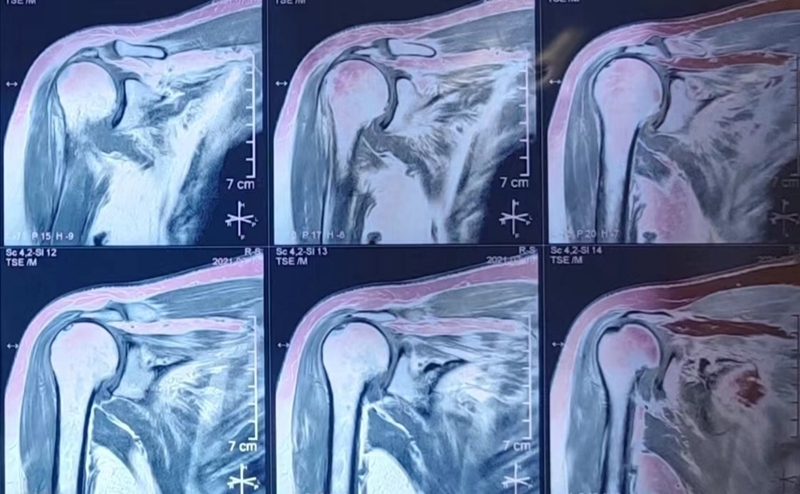

65岁女性,无明显诱因出现右肩疼痛、活动受限1年,外伤后加重2个月入院。术前右肩典型“假性瘫痪”,功能状态如图所示:

术前影像学检查示肱骨头向上移位,关节盂、肩峰和肱骨头退行性改变,典型肩袖撕裂性骨关节病(CTA)改变。